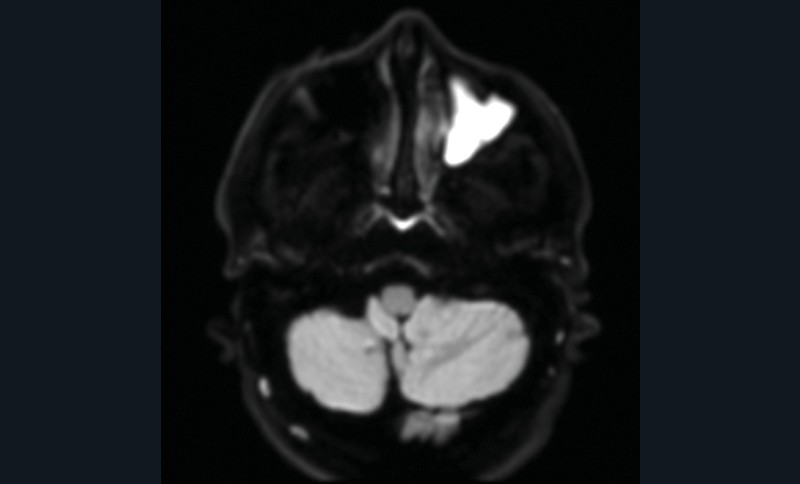

La tomodensitométrie des sinus retrouve un comblement complet unilatéral du sinus maxillaire gauche et des cellules ethmoïdales antérieures homolatérales, sans image de densité calcique intrasinusienne et sans lyse osseuse des parois (fig. 1). L’IRM montre un épaississement tissulaire de 23 mm de grand axe en regard du méat moyen gauche, avec un aspect de signal T2 hétérogène (fig. 2) et prenant le contraste en masse (fig. 3). Le comblement maxillaire gauche associé à un épaississement muqueux en cadre rehaussé correspond à une rétention en hypersignal en diffusion (fig. 4), avec diminution du coefficient apparent de diffusion (moyenne à 433 mm2/s) en faveur d’une pyocèle (fig. 5).